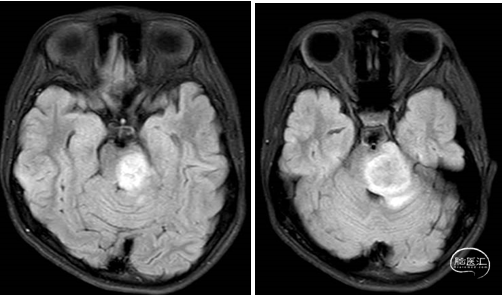

术前MRI

术后MRI